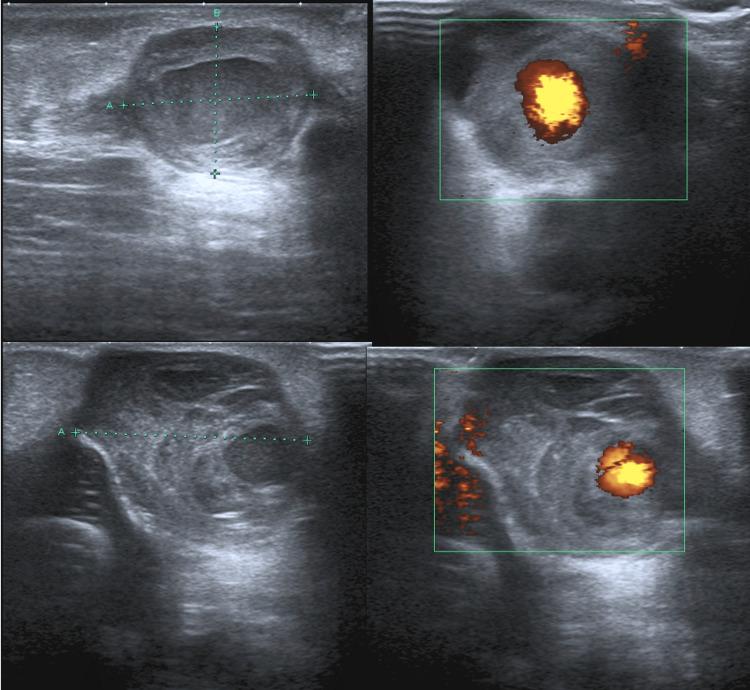

Pseudoaneurysm following percutaneous tendoachilles (TA) tenotomy is a rare complication found in children with congenital talipes equinovarus (CTEV). It is postulated that associated aberrant vascular anatomy in combination with CTEV may be the underlying aetiology. In this case report, we describe a case of a toddler who developed bilateral pseudoaneurysms following percutaneous tendoachilles tenotomy and explore the management and outcome in relation to this. Based on this case report and a review of the literature, the consistent clinical findings of swelling and/or discolouration due to pseudoaneurysm occur at three weeks post-tenotomy, and should raise suspicion for the diagnosis. Furthermore to the best of our knowledge, this is the first case report of bilateral pseudoaneurysms in the same setting, and we propose the possibility of an aberrant vessel arising from the peroneal artery that may be prone to injury.

经皮跟腱切断术后假性动脉瘤是先天性马蹄内翻足(CTEV)患儿中罕见的并发症。据推测,CTEV合并异常血管解剖结构可能是其潜在病因。在本病例报告中,我们描述了一名幼儿经皮跟腱切断术后出现双侧假性动脉瘤的病例,并探讨了相关的治疗方法及结果。基于本病例报告及文献回顾,假性动脉瘤导致的肿胀和/或变色等一致的临床症状出现在跟腱切断术后三周,应引起对该诊断的怀疑。此外,据我们所知,这是同一病例中双侧假性动脉瘤的首例病例报告,我们提出可能存在一条来自腓动脉的异常血管,该血管可能易于受伤。